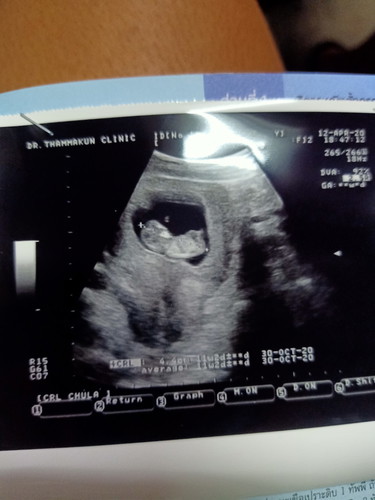

11สัปดาห์

ลุงหมอทักมาครบแล้ว แม่บอกไม่ถูกเลยค่ะดีใจมาก ครั้งแรกที่ได้เจอกัน

กำหนดคลอดเดือนตุลาคมใช่ไหมค่ะ